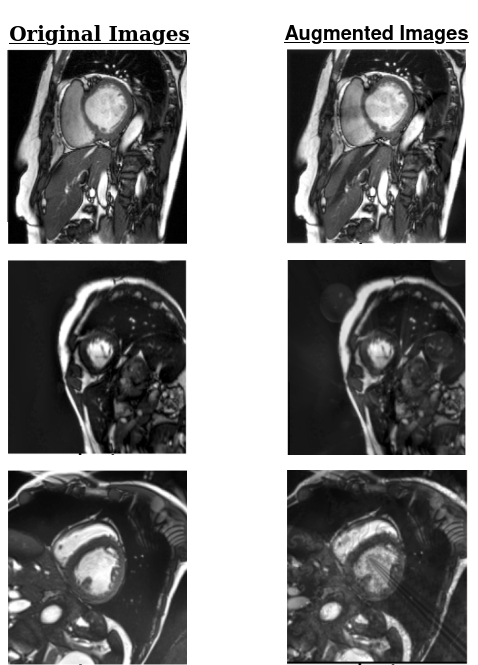

Refer to caption

Figure 3: Artifacted cardiac images. From left to right: Bias Artifact (showing as difference in brightness on different images areas), Ghosting Artifact (showing as idols due to movement of the organ or patient), Motion Artifact (showing as displacement), Spike Artifact (showing as stripes due to electromagnetic interference)

For our experiments we evaluate corruption robustness on the publicly available dataset the ACDC cardiac segmentation challenge dataset [45], consisting of a total of 100 heart MRI scans. Of the three-dimensional images, we make use of the slices corresponding to end-diastole and end-systole periods. The dataset is multi-labelled, consisting of annotations for left ventricle, myocardium and right ventricle. We evaluate on the following 4 types of corruptions created by TorchIO software [46]:

• Motion: Random ”motion”, which usually appears physiologically in MRI images due to organ motion.

• Spike: Random spike artifacts, also known as Herringbone artifacts, create stripes in different directions in the image space due to spikes generated in the machine’s electromagnetic field.

• Ghosting: Random displacement of an image ghost, usually due to cardiac motion, patient motion during the examination, or blood flow.

• Bias Field: Random fluctuations in image intensity usually due to the in-homogeneity of the MRI machine’s field.

Examples of the images are shown in Figure 3.